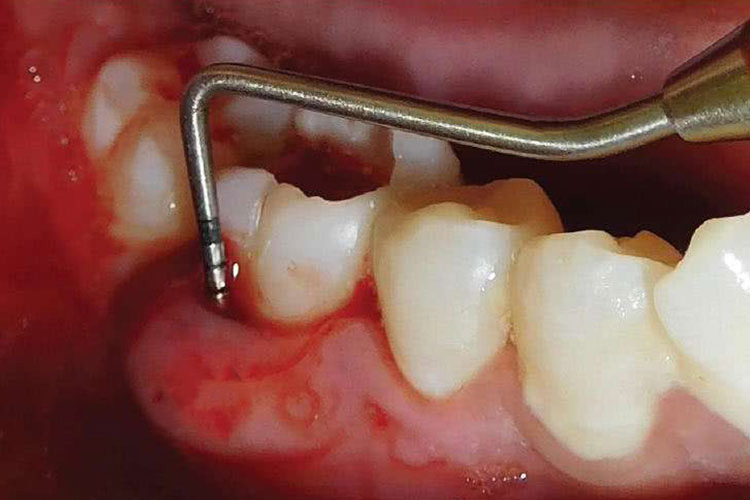

急性牙周脓肿:治疗原则是止痛、防止感染扩散以及使脓液引流。在脓肿初期脓液尚未形成前,可轻轻清除大块牙石,冲洗牙周袋,将防腐抗菌药引入袋内,必要时全身给以抗生素或支持疗法。当脓液形成且局限、出现波动时,可在牙周袋内或牙龈表面引流。并应彻底冲洗脓腔,或在局麻下彻底进行龈下清创术。